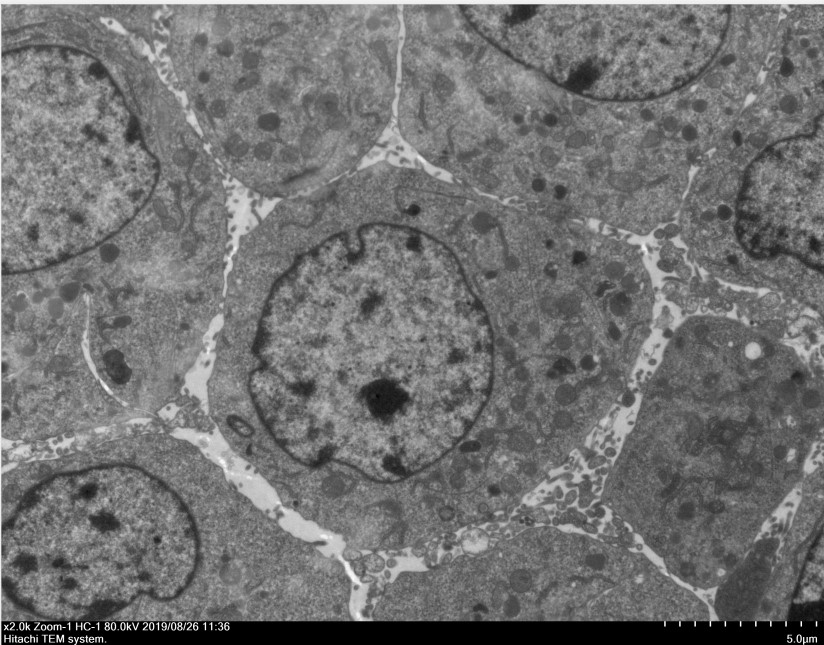

四、成果展示

原始掃描電鏡圖片,倍數依據實際情況選擇合適放大倍數,每個倍數2-3張